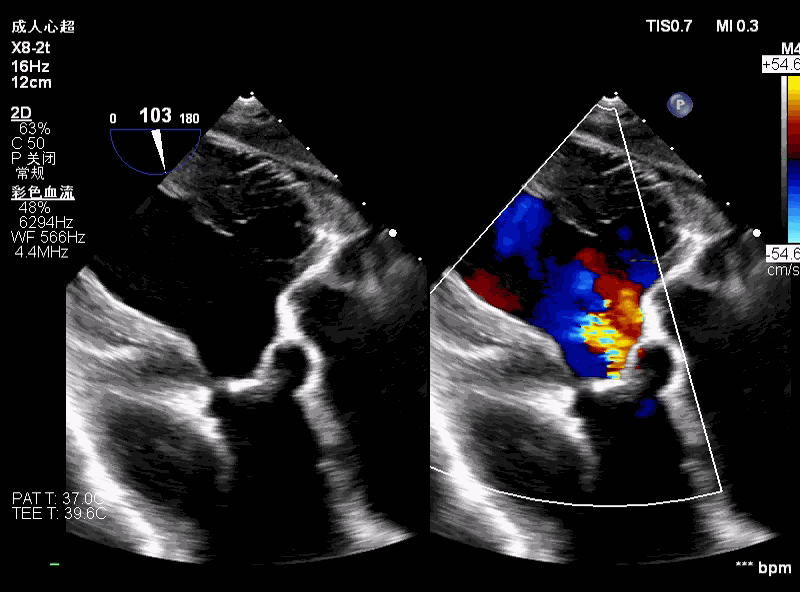

隐约可见“无冠窦”后部更深窦底,位于“无冠窦”下约6mm,参考该位置后进行0位定位,无起搏逐步释放至工作位,瓣膜无明显位移表现,瓣膜形态压缩良好,造影评估无反流。准备释放瓣膜。

无张力释放,脱钩后瓣膜略微下滑,约位移瓣环下4~5mm位置,瓣膜整体形态良好,造影评估无可见反流。

超声评估,微量瓣周反流,二尖瓣工作良好,植入位置理想。